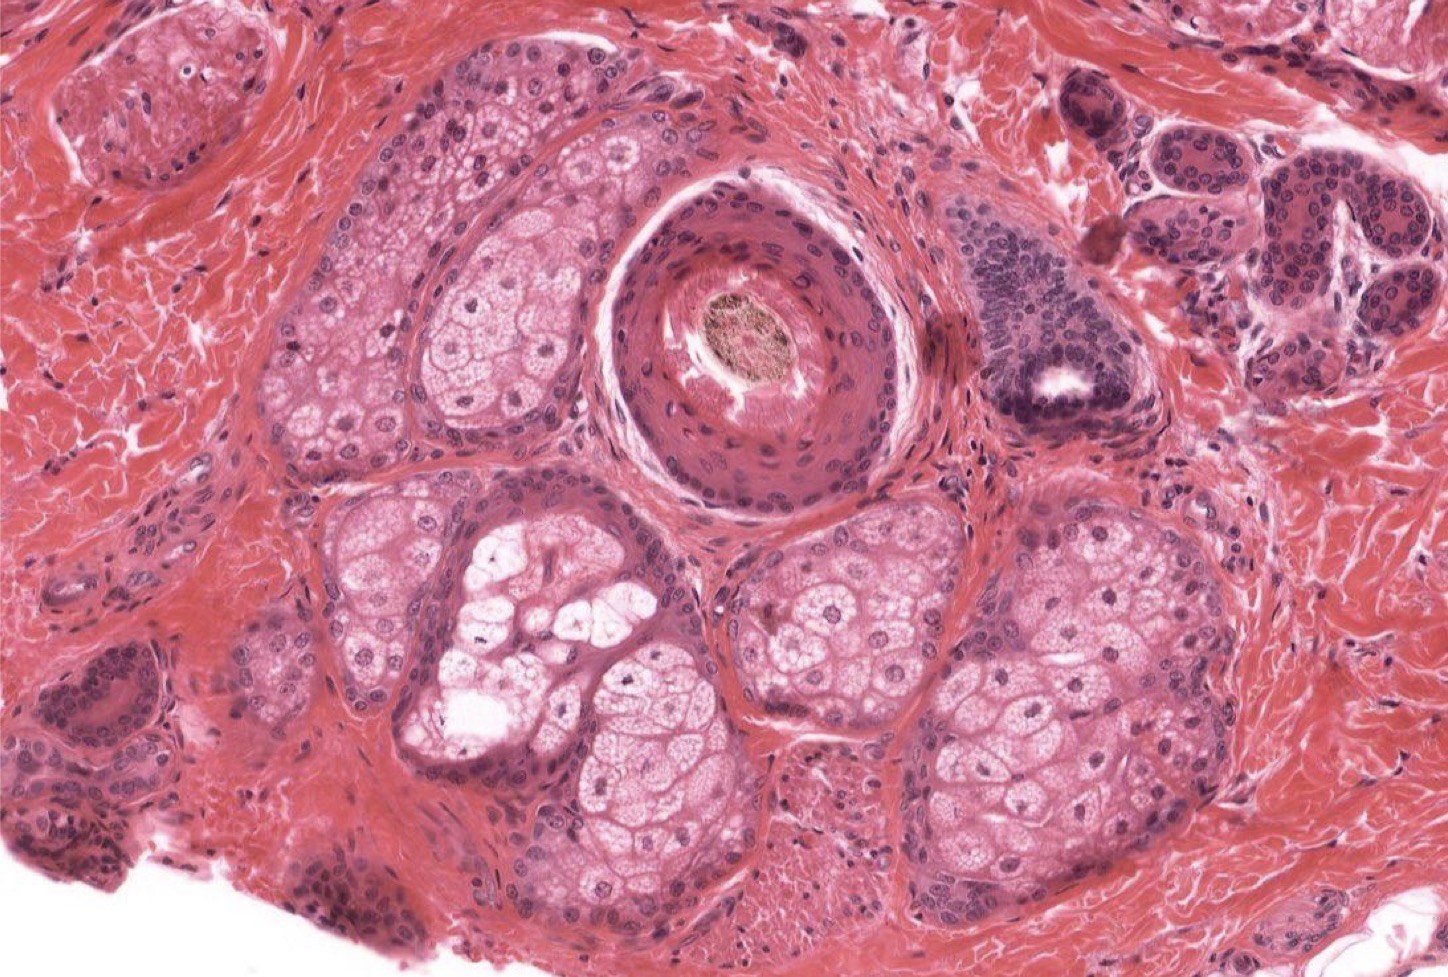

Identify the Structure

Pacinian Corpuscle